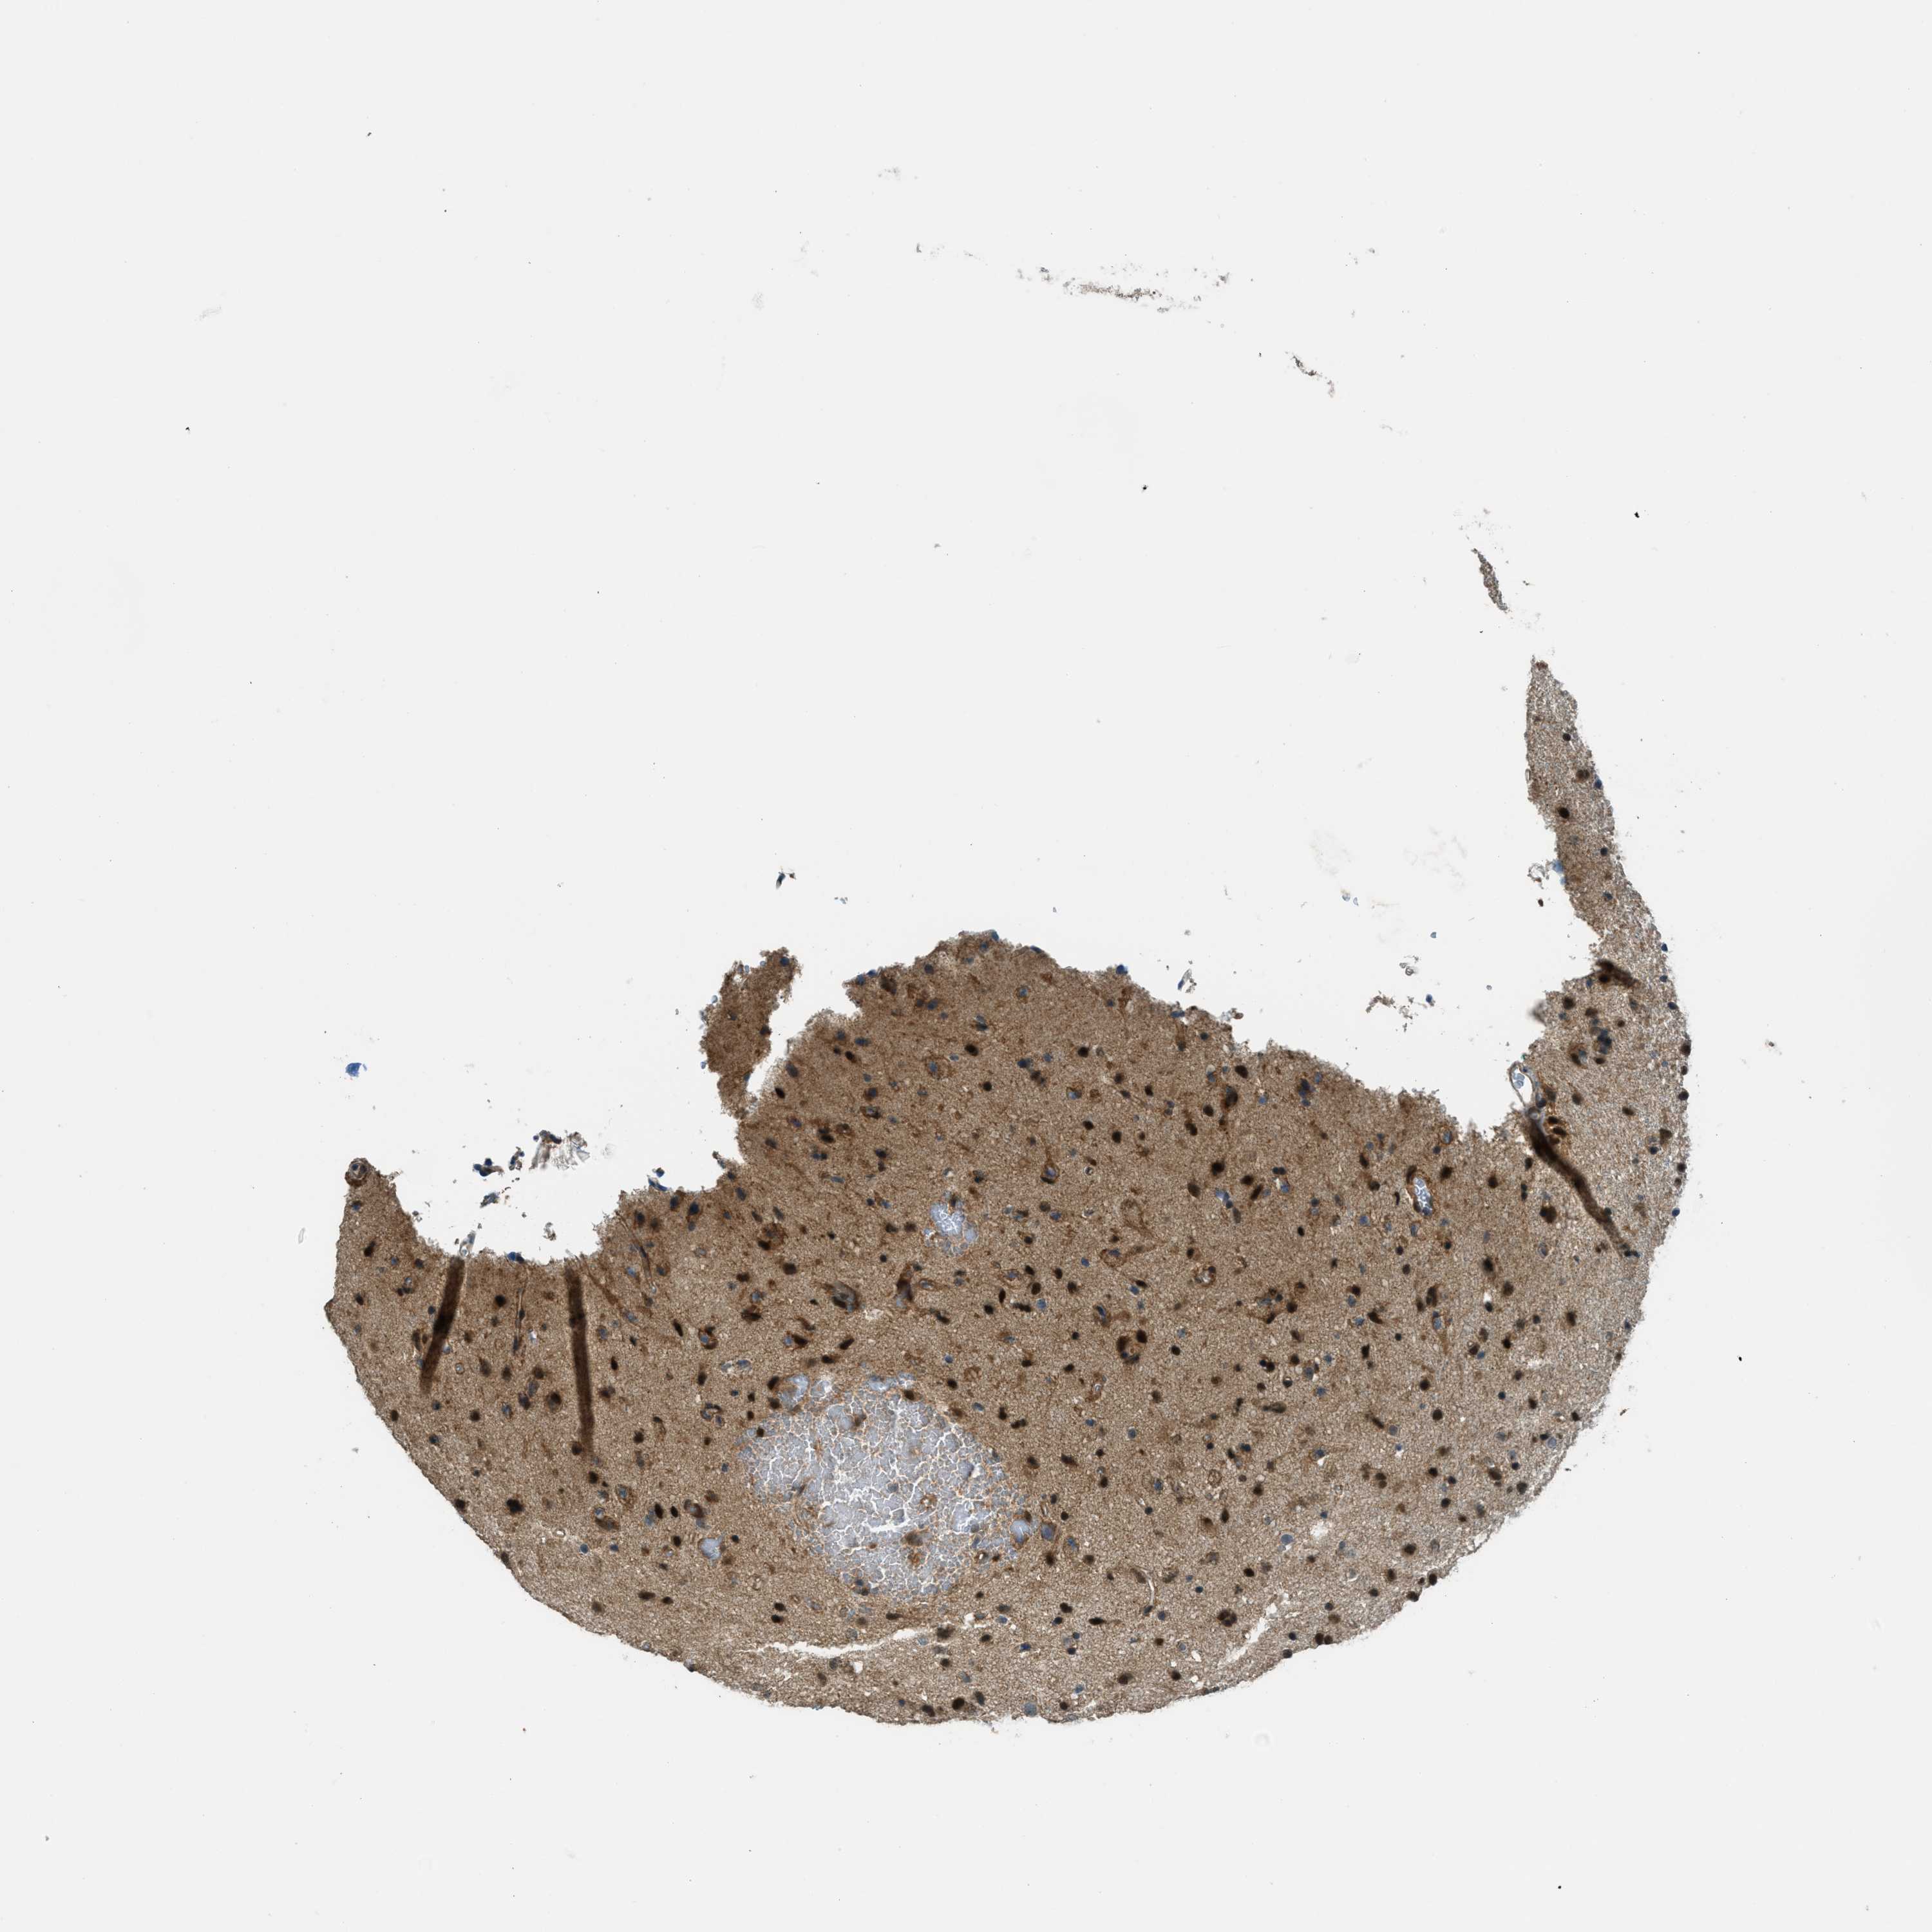

GLIOMA - Protein expressioni

A mouse-over function shows sample information and annotation data. Click on an image to view it in a full screen mode. Samples can be filtered based on level of antibody staining by selecting one or several of the following categories: high, medium, low and not detected. The assay and annotation is described here.

Note that samples used for immunohistochemistry by the Human Protein Atlas do not correspond to samples in the TCGA dataset.

Antibody stainingi

Antibody staining in the annotated cell types in the current human tissue is reported as not detected, low, medium, or high, based on conventional immunohistochemistry profiling in selected tissues. This score is based on the combination of the staining intensity and fraction of stained cells.

Each image is clickable and will lead to virtual microscopy that enables deeper exploration of all samples and also displays staining intensity scores, fraction scores and subcellular localization as well as patient and tissue information for each sample.

Antibody HPA036356

Antibody CAB004986

Antibody CAB017025

Staining

High

Medium

Low

Not detected

Intensity

Strong

Moderate

Weak

Negative

Quantity

>75%

75%-25%

<25%

None

Location

Nuclear

Cytoplasmic/membranous

Cytoplasmic/membranous,nuclear

Glioma, malignant, Low grade

Glioma, malignant, High grade

Glioma, malignant, NOS